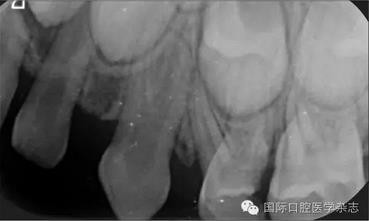

根尖X線片檢查偶然發(fā)現(xiàn):左側(cè)上頜乳尖牙呈雙根,髓腔寬大,牙根自接近根中1/3起至根尖分為明顯的近中及遠(yuǎn)中2個(gè)牙根(圖2)?;純杭议L知情同意后,拍攝其他3張乳尖牙根尖片,以觀察牙根是否有異常。X線片示:右側(cè)上頜乳尖牙呈雙根,且形態(tài)、大小及根分叉位置與左側(cè)相似(圖3)。雙側(cè)下頜乳尖牙的形態(tài)及牙根未見異常。詢問病史了解到,患兒體健,足月順產(chǎn),其母妊娠期間無感染或服藥史,患兒嬰幼兒期無外傷史,無兄弟姐妹。

圖2 左側(cè)上頜乳尖牙X線片

Fig 2 Maxillary leftprimary canine radiograph

圖3 右側(cè)上頜乳尖牙X線片

Fig 3 Maxillary right primary canine radiograph